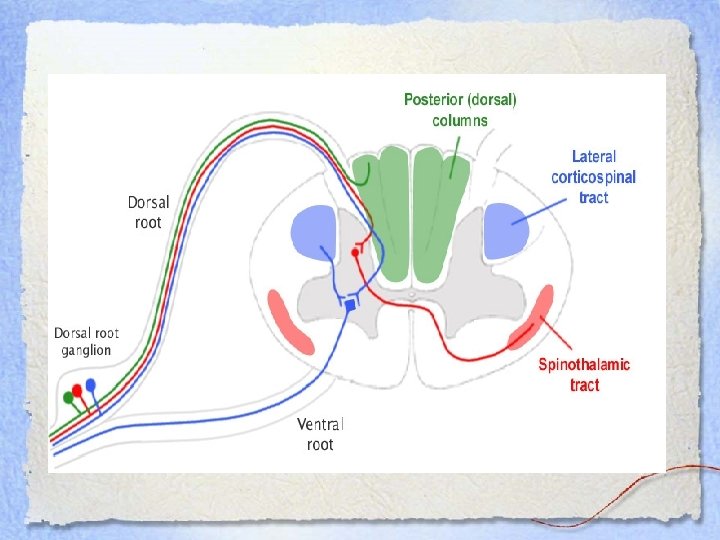

Neuroanatomy • Corticospinal tracts • Spinothalamic tracts • Dorsal (posterior) columns

Neuroanatomy • Corticospinal tracts • Spinothalamic tracts • Dorsal (posterior) columns

Corticospinal Tract • Descending motor pathway • Forms the pyramid of the medulla • In the lower medulla, 90% of fibers decussate and descend as the lateral corticospinal tract • Synapse on LMN in the spinal cord • 10% that do not cross descend as the ventral corticospinal tract • Damage to this part cause ipsilateral UMN findings

Corticospinal Tract • Descending motor pathway • Forms the pyramid of the medulla • In the lower medulla, 90% of fibers decussate and descend as the lateral corticospinal tract • Synapse on LMN in the spinal cord • 10% that do not cross descend as the ventral corticospinal tract • Damage to this part cause ipsilateral UMN findings

Spinothalmic Tract • Ascending sensory tract from skin and muscle via dorsal root ganglia to cerebral cortex • Temperature and pain sensation • Damage to this part of the spinal cord causes: – Loss of pain and temperature sensation in the contralateral side – Loss begins 1 -2 segments below the level of the lesion

Spinothalmic Tract • Ascending sensory tract from skin and muscle via dorsal root ganglia to cerebral cortex • Temperature and pain sensation • Damage to this part of the spinal cord causes: – Loss of pain and temperature sensation in the contralateral side – Loss begins 1 -2 segments below the level of the lesion

Dorsal (Posterior) Columns • Ascending neurons that do not synapse until they reach the medulla at which point they cross the midline to the thalamus • Transmits vibration and proprioceptive information • Damage will cause ipsilateral loss of vibration and position sense at the level of the lesion

Dorsal (Posterior) Columns • Ascending neurons that do not synapse until they reach the medulla at which point they cross the midline to the thalamus • Transmits vibration and proprioceptive information • Damage will cause ipsilateral loss of vibration and position sense at the level of the lesion

Light touch… • Transmitted through both the dorsal columns and the spinothalamic tracts • Lost entirely ONLY if both tracts are damaged

Light touch… • Transmitted through both the dorsal columns and the spinothalamic tracts • Lost entirely ONLY if both tracts are damaged